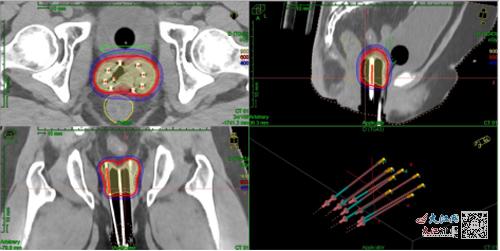

圖為后裝靶區及劑量

4月,周女士因月經淋漓不盡被確診為宮頸癌,在當地醫院行宮頸癌根治術后,術后病理分期為IIIC1p期。根據手術病理結果,周女士術后需要補充輔助性放化療。根據復查的影像學結果,腫瘤科、婦產科專家聯合進行婦科查體,確定患者原宮頸及宮旁有腫瘤組織殘留,同時無再次手術機會。為進一步提高治療療效,盡可能減輕副作用,醫務人員對患者行3D打印三維后裝及組織間插植放療,并由腫瘤科專家成功為周女士完成了第一次3D打印三維后裝及組織間插植放療。

3D打印后裝模具制作主要包括圖像采集、預計劃制定、3D模具設計及打印等過程,設計完成經醫生確認后,將數據傳至3D打印機,使用PLA材料打印出模具。3D打印模具可以降低操作難度,減小重復誤差,降低膀胱及直腸的近期發生不良反應情況,通過預計劃設置插植針道,避免周圍器官損傷,控制插植針進針方向及深度、降低插植技術難度,彌補通用施源器不足之處。在對臨床上因腫瘤位置及解剖結構等導致施源器放置困難的患者,多項研究均證實3D打印模板的劑量學優勢。